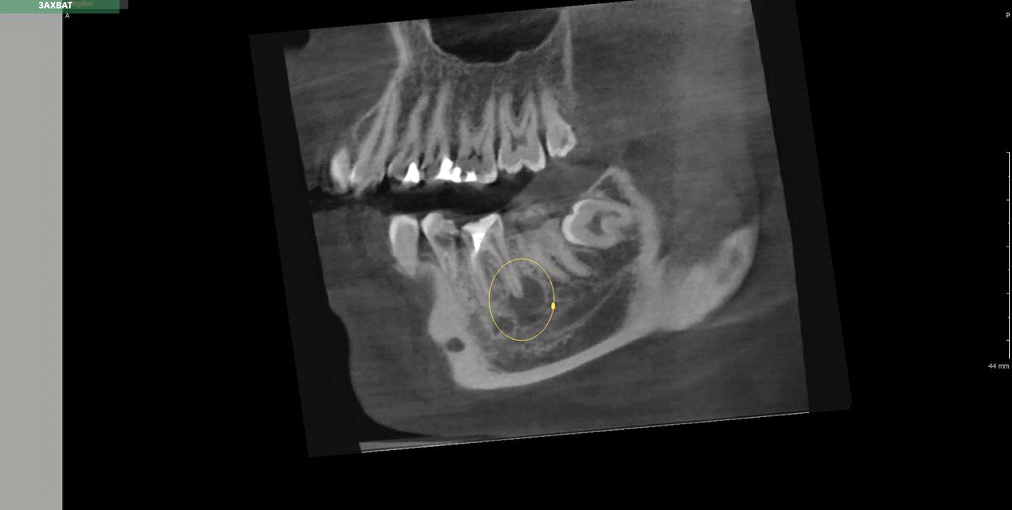

Здесь есть тень воспалительного процесса рядом с верхушкой корня. Не перепутайте с гайморовой пазухой (большой темный овал в верхней части кадра).